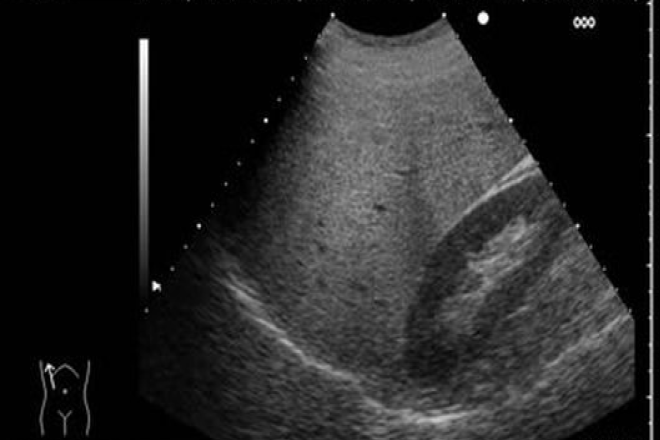

Al desplazar el transductor hacia la derecha, por debajo del reborde costal, se observa una imagen donde el hígado ocupa la mayoría de la pantalla, incluyendo el lóbulo derecho y parte del izquierdo, delimitado en su parte posterior por el diafragma.